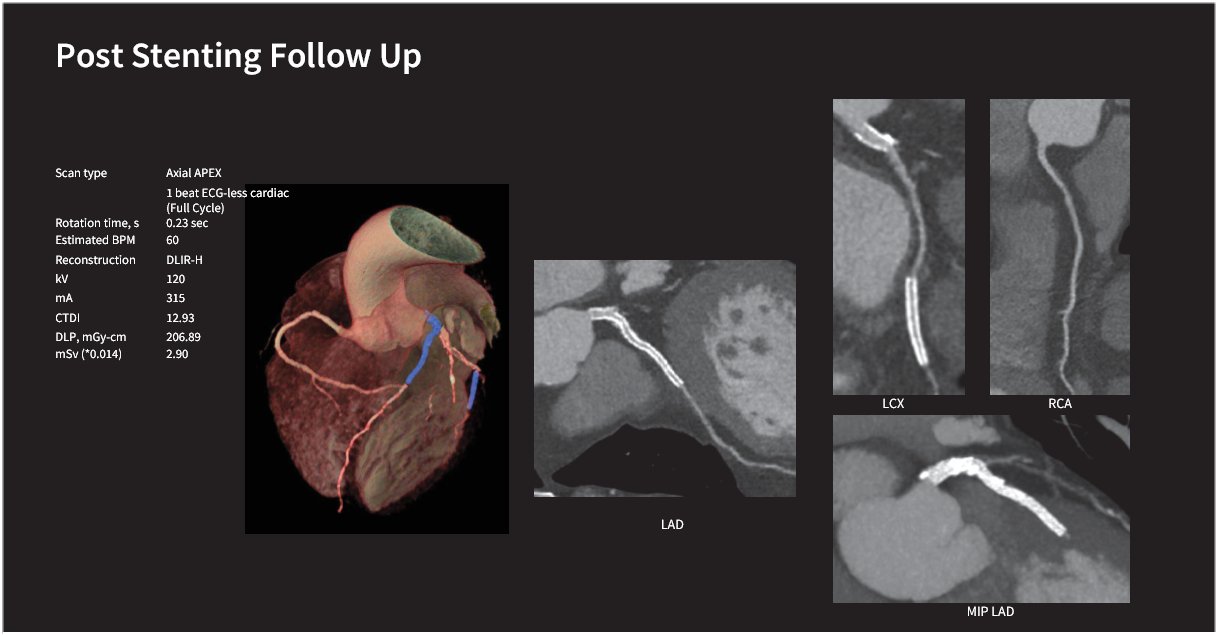

Innovation importante pour les urgences : ECG Less, matelas coquille, dans le cas d’examen d’urgence difficile, un simple monitoring au bout du doigt et l’acquisition cardiaque est mise en action ! ! !

TAVR : voie radiale Contrôle d’un Stent après sa pose

Visualisation intra stent sans artéfact, très important en cas de thrombose, et avec une grande précisions